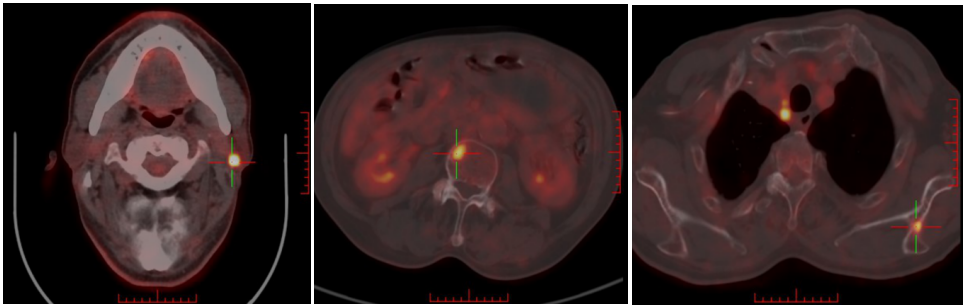

2022-06-28日复查PET-CT:1、双侧头臂血管周围、右侧气管食管沟、纵隔(2R、2L、3a、4R、4L、5、6、7区)右侧肋膈角见多发FDG代谢增高淋巴结,部分淋巴结坏死,结合病史,考虑多发淋巴结转移,病变数目较前增多、体积增大。L3椎体右侧、左侧肩胛冈FDG代谢增高,考虑骨转移。2、右肺上叶前段胸膜下环形FDG代谢增高病变中心伴有坏死,病变较前稍增大;左肺上叶舌段及下叶内前基底段、右上叶及下叶多发结节,部分伴FDG代谢增高,较前未见明显变化;右侧胸膜增厚伴右侧胸膜增厚伴FDG代谢增高,较前增厚,右侧胸腔积液较前减少。余未见转移征象。综上:多发淋巴结转移,新发骨转移,考虑PD。